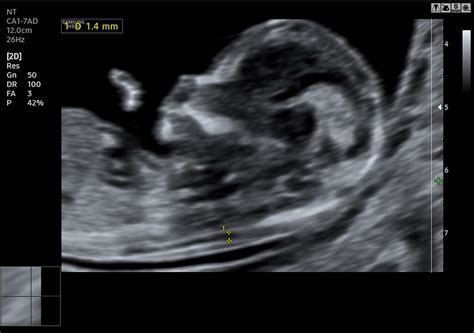

Az ultrahang technika segítségével az embrió szívműködése már a terhesség korai szakaszában azonosítható. Az embrió szívfrekvenciája az első három hónapban jellegzetesen változik: a 8. hét előtt percenként 100, utána akár 160-ra emelkedik, majd a 12. héttől állandósul az alapfrekvencia 120 körüli értéken.

Ahhoz, hogy a babának lehessen szívhangja, legalább a szívcsőnek ki kell alakulnia. Vagyis ebben az esetben is igaz, hogy nem lehet kapkodni, ki kell várni mindennek az idejét. Azok a kismamák, akik túlságosan korán mennek az orvoshoz, belefuthatnak egy ilyen helyzetbe. Hogy mi a túl korán? A magzat 6 hetes koránál a szívcső pulzálását már lehet észlelni az ultrahangon, előtte azonban ijesztő lehet a tény, hogy nincsen szívhang. A fejlődési ütem sajátossága, hogy a magzat foganásától 6 hétre szükség van, hogy a szív elkezdhessen kialakulni, és megkezdhesse életen át tartó munkáját. A gond nem is azzal van, hogy a kismama kivárja az időt, hanem inkább azzal, hogy elszámolja magát.

Az ovuláció a legalkalmasabb időszak a fogantatásra, így egy - két napos menzesz kimaradás már jelezheti a várandósságot. A pálca is elszíneződhet, de ekkor még csak 2-3 hetes magzatról lehet szó. Ha a kismama azonnal jelentkezik az orvosához, és időpontot is kap, akkor egy nagyjából 4 hetes magzattal kerül az első ultrahangjára, ami ugyan kimutatható, de a fejlődése még nem lépett abba a szakaszba, amikor már szívhang is tapasztalható. Ez azt is jelenti, hogy ha vissza kell menni UH vizsgálatra az orvoshoz, akkor a szívhang megjelenése pontosíthatja a fogantatás dátumát is.